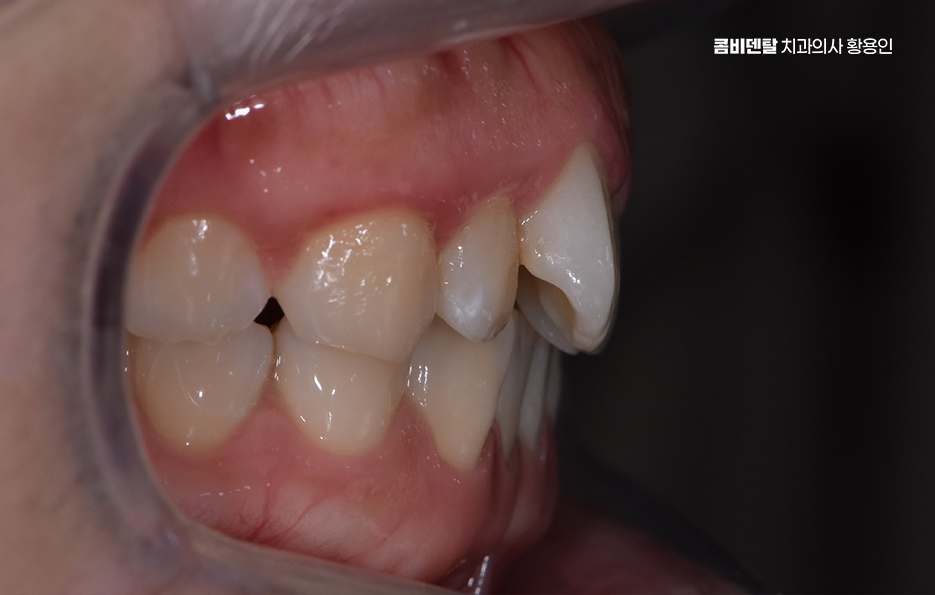

치아 교정을 할 때 통증을 느끼는 정도는 교정 치료의 방식이나 사용되는 장치, 발치 여부 등에 따라서도 차이가 있어요. 치아 교정은 치아를 이동시키면서 새로운 위치에 자리 잡도록 하는 과정이기 때문에 일정한 압력이 가해지면서 불편함이나 통증이 생길 수 있지만 이러한 통증은 시간이 지나면서 점차 완화되기 때문에 너무 걱정할 필요는 없으며 교정 치료를 받는 동안 치아교정 통증 줄이는 방법 또한 있기 때문에, 교정 과정을 좀 더 편안하게 진행할 수 있도록 여러 가지 방법을 활용하신다면 좋을 거예요

교정 통증이 발생하는 가장 큰 이유는 치아가 이동하면서 주변 조직과 신경이 자극을 받기 때문으로 치아는 잇몸 뼈와 치주 인대에 의해 고정되어 있는데, 교정 장치를 부착하면 치아가 천천히 이동하면서 치주인대에 압박이 가해지고, 이로인해 혈류량이 감소하면서 신경을 자극하는 대사물질이 생성되어 통증이 발생하고, 이 과정에서 압박되는 쪽 뼈가 녹고, 반대쪽 여유공간에서 뼈가 재 형성되면서 통증이 발생하는 거예요.

교정 장치의 종류에 따라서도 통증의 정도가 다를 수 있는데 일반적인 금속 브라켓을 사용하는 경우, 초기에는 금속이 입 안쪽에 닿으면서 불편함을 느낄 수 있어요. 특히 교정 와이어를 조절할 때마다 일정한 힘이 가해지기 때문에 몇 일 동안은 씹는 것이 불편할 수도 있지만 반면, 클리피씨 같은 자가 결찰형 브라켓을 사용하는 경우, 마찰력이 줄어들면서 치아 이동 속도가 상대적으로 빠르고, 통증이 덜하다고 느낄 수 있어요. 또한 투명 교정이나 인비절라인 같은 경우에는 탈착이 가능하고 교정기로 인한 통증이 일반교정에 비해 상대적으로 덜한 편이라는 특징이 있어요